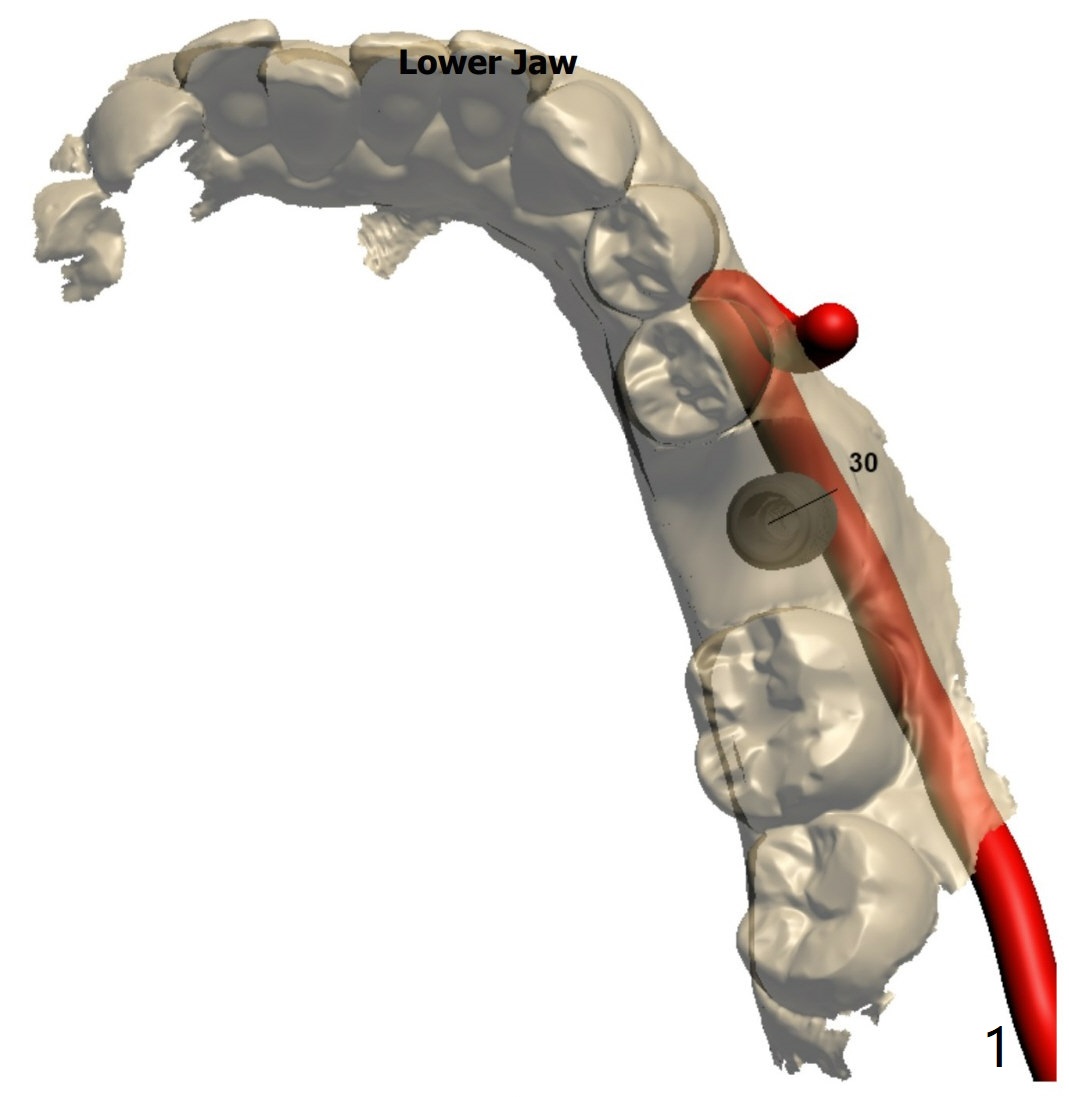

A 53-year-old man. PRFx1. Place 5x11 mm Tatum tapered implant (9 mm in bone).